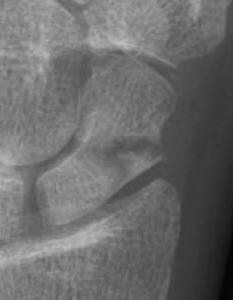

Scaphoid waist fracture 1 mm displaced

Scaphoid fracture with significant displacement

Scaphoid proximal pole fracture